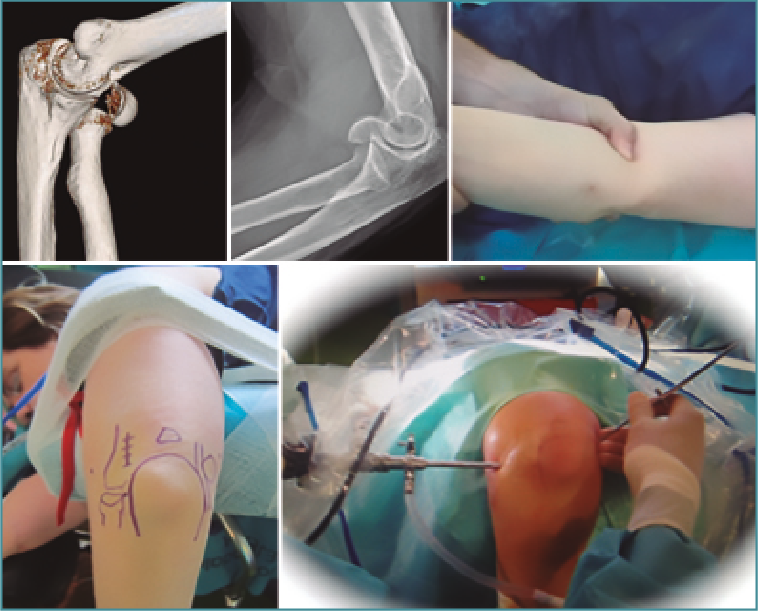

El uso del artroscopio como complemento para el tratamiento de las fracturas articulares –rodilla y muñeca especialmente– es una práctica generalizada en muchos servicios de traumatología, pero en la actualidad su uso sigue siendo infrecuente para las fracturas del área del codo (Figura 1).

Figura 1. Fractura de codo asistida por artroscopia.

Nuestra experiencia durante el periodo 2007-2017 es de 110 artroscopias de codo, realizadas en distintos centros sanitarios (sanidad pública y privada). Si bien algunas indicaciones han sido las clásicas (extracción de cuerpos libres, epicondilalgias, artrolisis, valoración de osteocondritis disecante, biopsia sinovial y sinovectomía, así como el diagnóstico de condromatosis sinovial), desde hace años valoramos la inestimable ayuda del artroscopio para las fracturas articulares de esta compleja articulación (Figura 1).